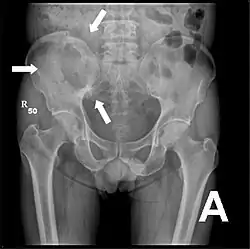

Röntgenaufnahme des Beckens eines Patienten mit Prostatakarzinom: Multiple osteoplastische Knochenmetastasen, insbesondere im Kreuzbein, aber auch im Darmbein, vor allem links (also rechts im Bild), am Sitzbeinhöcker links und im proximalen Oberschenkelknochen links. Nebenbefundlich zeigt sich eine Hüftgelenksarthrose rechts (also links im Bild). -

Röntgenaufnahme des Beckenraums osteolytischer Metastasen. Die Metastasen sind in beiden Oberschenkelknochen und am Becken selbst.